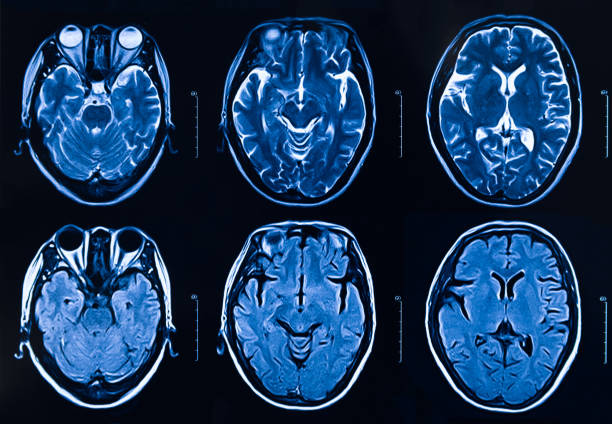

뇌로 이어져 있는 혈관이 막히거나 막힘으로 인하여 터지면서 발생하는 뇌 질환으로 뇌 혈관이 차단되면서 혈액 운반이 정상적이지 않으면 뇌 손상이 발생합니다. 이로 인하여 각종 합병증을 유발하는데 호흡 장애나 언어 장애 등의 후유증 또한 나타나며 심가할 경우 심정지로 가며 생명을 위협할 수 있는 질환으로 미리 전조증상에 대해 알아두고 골든타임에 조치를 받는 것이 중요합니다.

뇌졸중은 뇌경색인지 뇌출혈인지에 따라 판단 역시 다르게 나타납니다. 뇌줄중 환자의 열 명 중 여덟 명은 뇌경색을 가지고 있으며 심장에서 혈액 이동을 막는 혈전이 생기기 때문에 뇌에도 원활한 혈액 공급이 되지 않아 뇌혈관이 막히며 문제가 발생하며 뇌출혈은 열 명 중 두 명꼴로 나타나는데 뇌 신경 손상만 있는 것이 아니라 혈액이 뇌 속에 고여 조직을 압박하거나 충격을 주기도 하는데 결국 혈액을 운반하는 혈관 건강이 좋지 않아지면서 나타나는 뇌졸중 역시 서구화된 식습관과 생활습관으로 고지혈증과 같은 심혈관계 질환으로 동맥경화가 유발되며 나타나고 있어 주의가 요구됩니다.